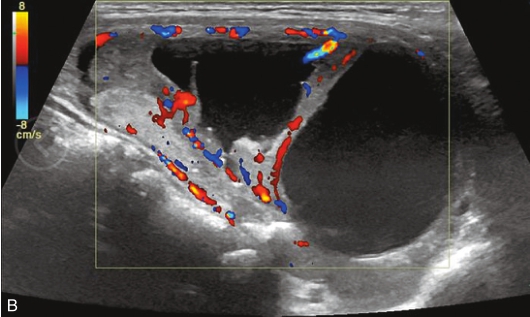

甲状腺右叶中部可见一囊实性结节,大小约2.1cm×1.8cm×1.5cm,形状尚规则,边界尚清楚,分布不均匀,后方回声无变化,CDFI显示结节内可见丰富的血流信号,见图1-3-20。

图1-3-20 甲状腺腺瘤伴囊性变示意图

A.甲状腺右叶纵切面示甲状腺右叶中下部囊实性结节,形态规则,边界清楚;B.CDFI显示其内部分可见丰富的血流信号,部分未见血流信号

注射造影剂后,12s病灶实性部分稍晚于周围甲状腺组织开始增强,病灶增强模式为等增强,增强形态为不均匀增强,15s病灶实性部分增强达峰值,20s病灶实性部分增强开始减退,35s病灶实性部分呈不均匀低增强,整个造影过程中病灶内囊性部分始终呈无增强,见图1-3-21、ER1-3-10。

图1-3-21 甲状腺腺瘤伴囊性变造影图像

A.注入造影剂12s;B.注入造影剂15s;C.注入造影剂20s;D.注入造影剂35s